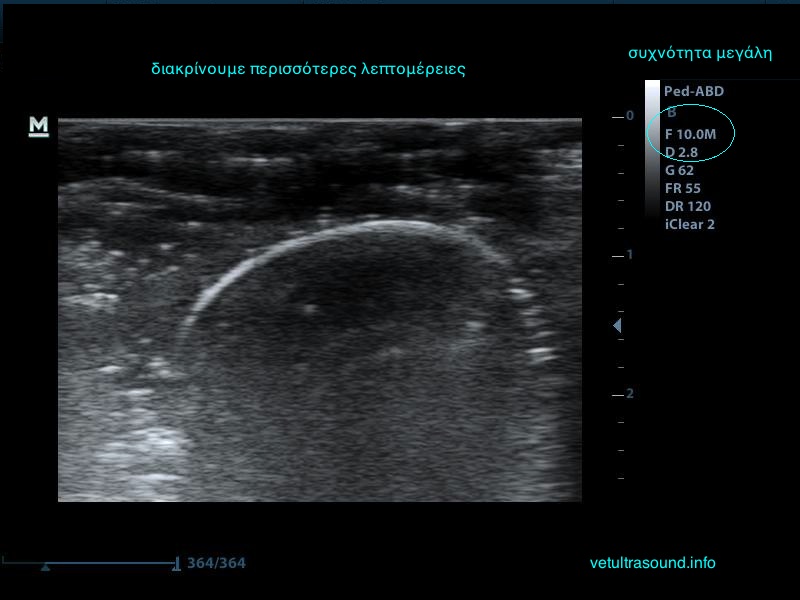

3) Τη συχνότητα, δηλαδή όσο πιο μεγάλη είναι αυτή, τόσο πιο πολλές λεπτομέρειες βλέπουμε αλλά ταυτόχρονα αυξάνονται τα τεχνουργήματα από αέρα και άλλες δομές. Οι αρμονικές βοηθούν στην καταστολή αυτών των τεχνουργημάτων.